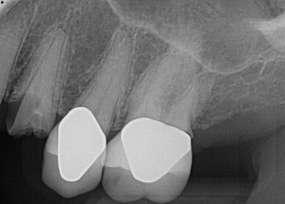

Fig 17. 12-week postoperative radiograph.

Figure 17

The final impression appointment follows the light-load phase, provided the implant is stable and the soft tissue is acceptable to the clinician. Polyvinyl putty and light-body impression materials were used in this case; analog casts and final full-zirconia full crowns were fabricated (Figure 16). The patient provided feedback that chewing was comfortable and without food impactions. Keratinized gingival cuff was developed, and natural-tooth contours for the restorations mimicked what is normally found in human dentition. The healed bone surrounding the ceramic dental implant was similar in density and crestal levels in comparison with the adjacent natural teeth, evident in the radiographic evaluation (Figure 17). Final long-term restorations at the gingival crest and restoration interfaces were also consistent in optimum periodontal health and gingival height. Arch-form integrity was upheld and occlusion was managed; osseointegration and light-load principles optimized the success of the restorations, and an acceptable, harmonious esthetic outcome was achieved for the patient.